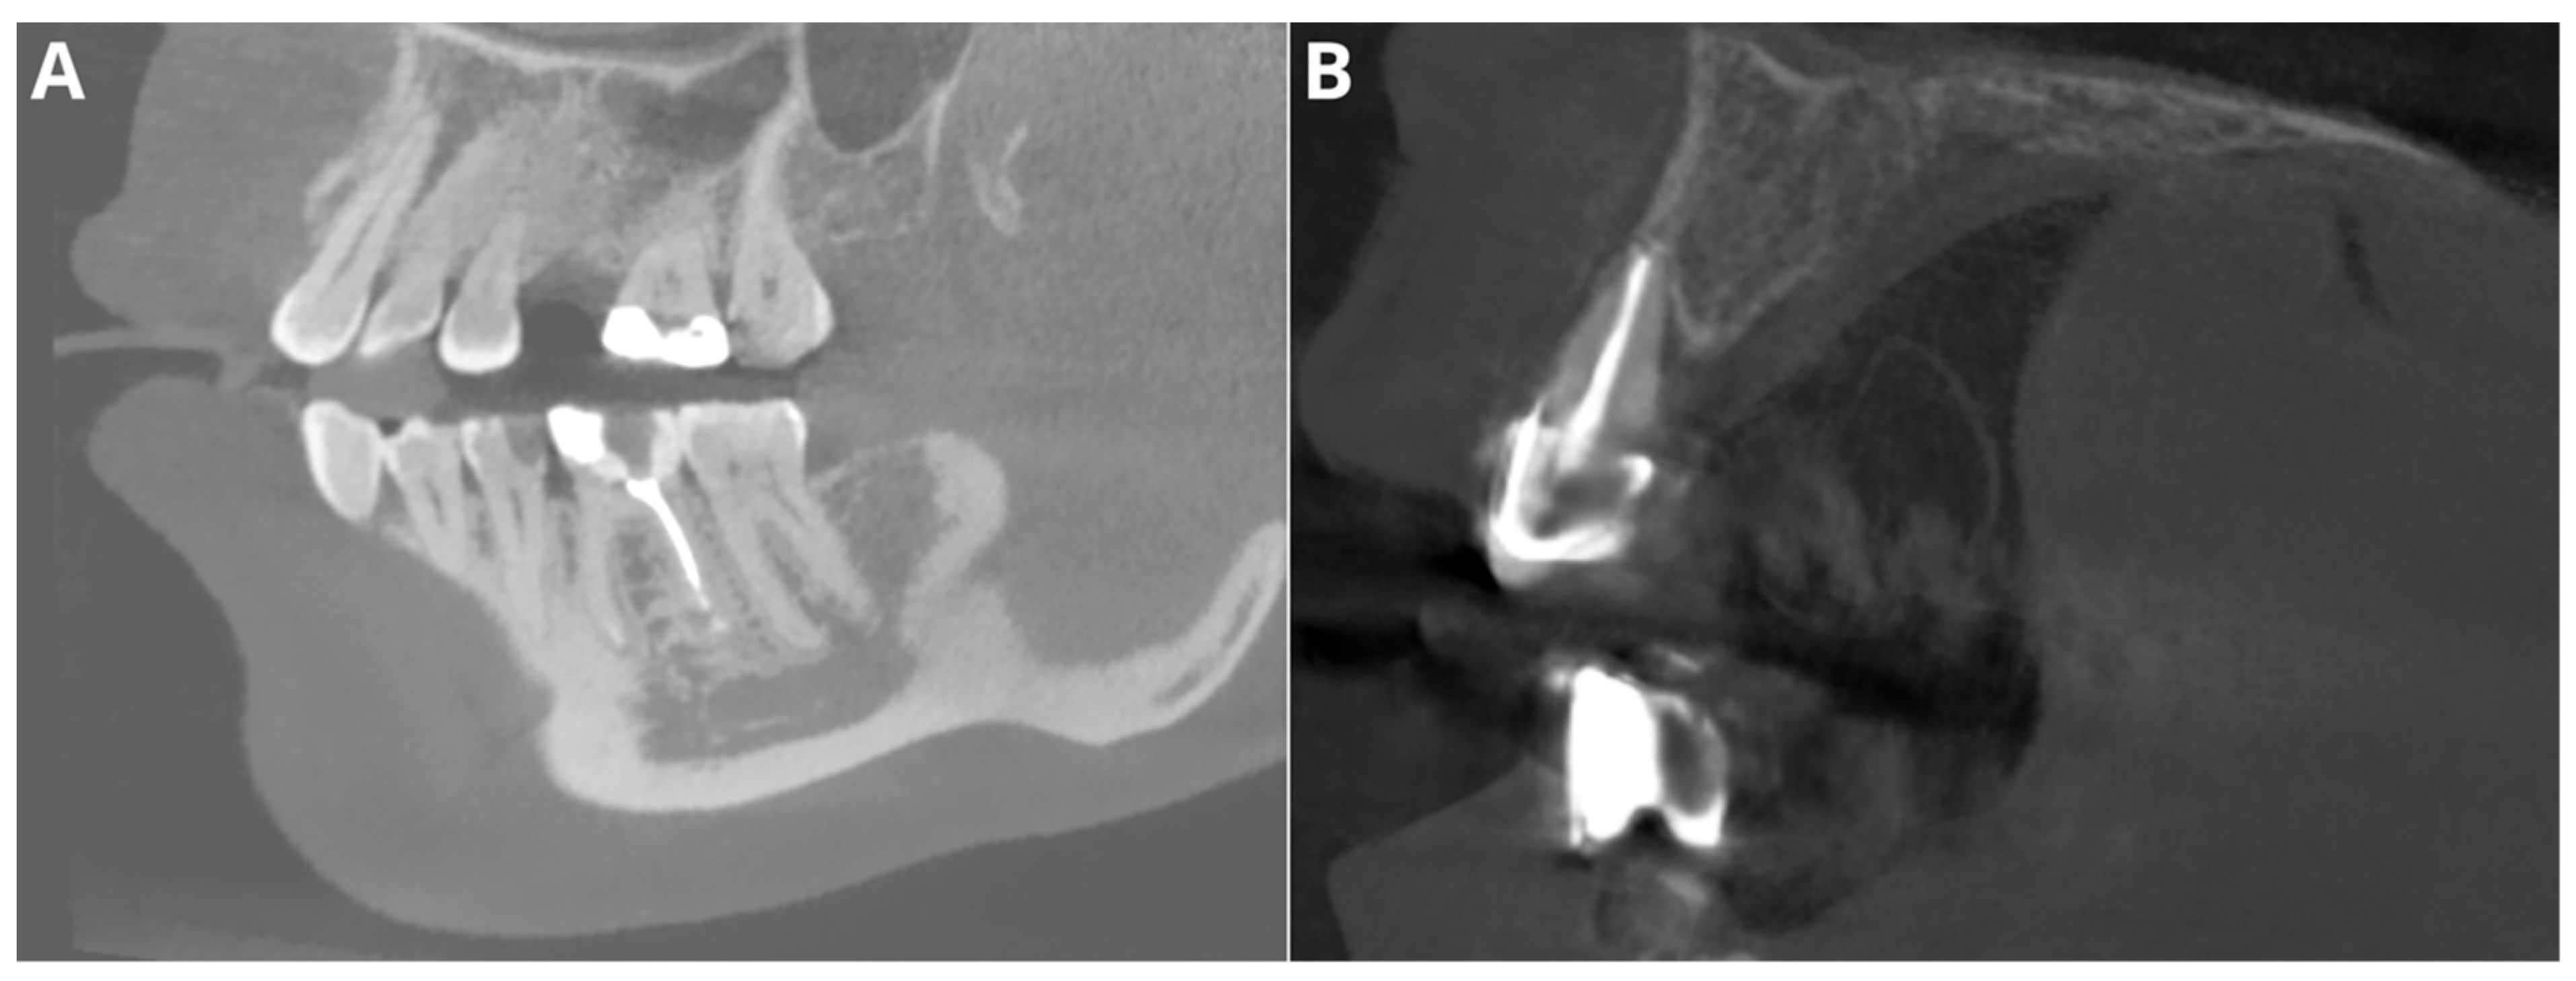

Figure 3.

Two of the false negative diagnoses involved overfilling. (A)—tooth 46; (B)—tooth 12.